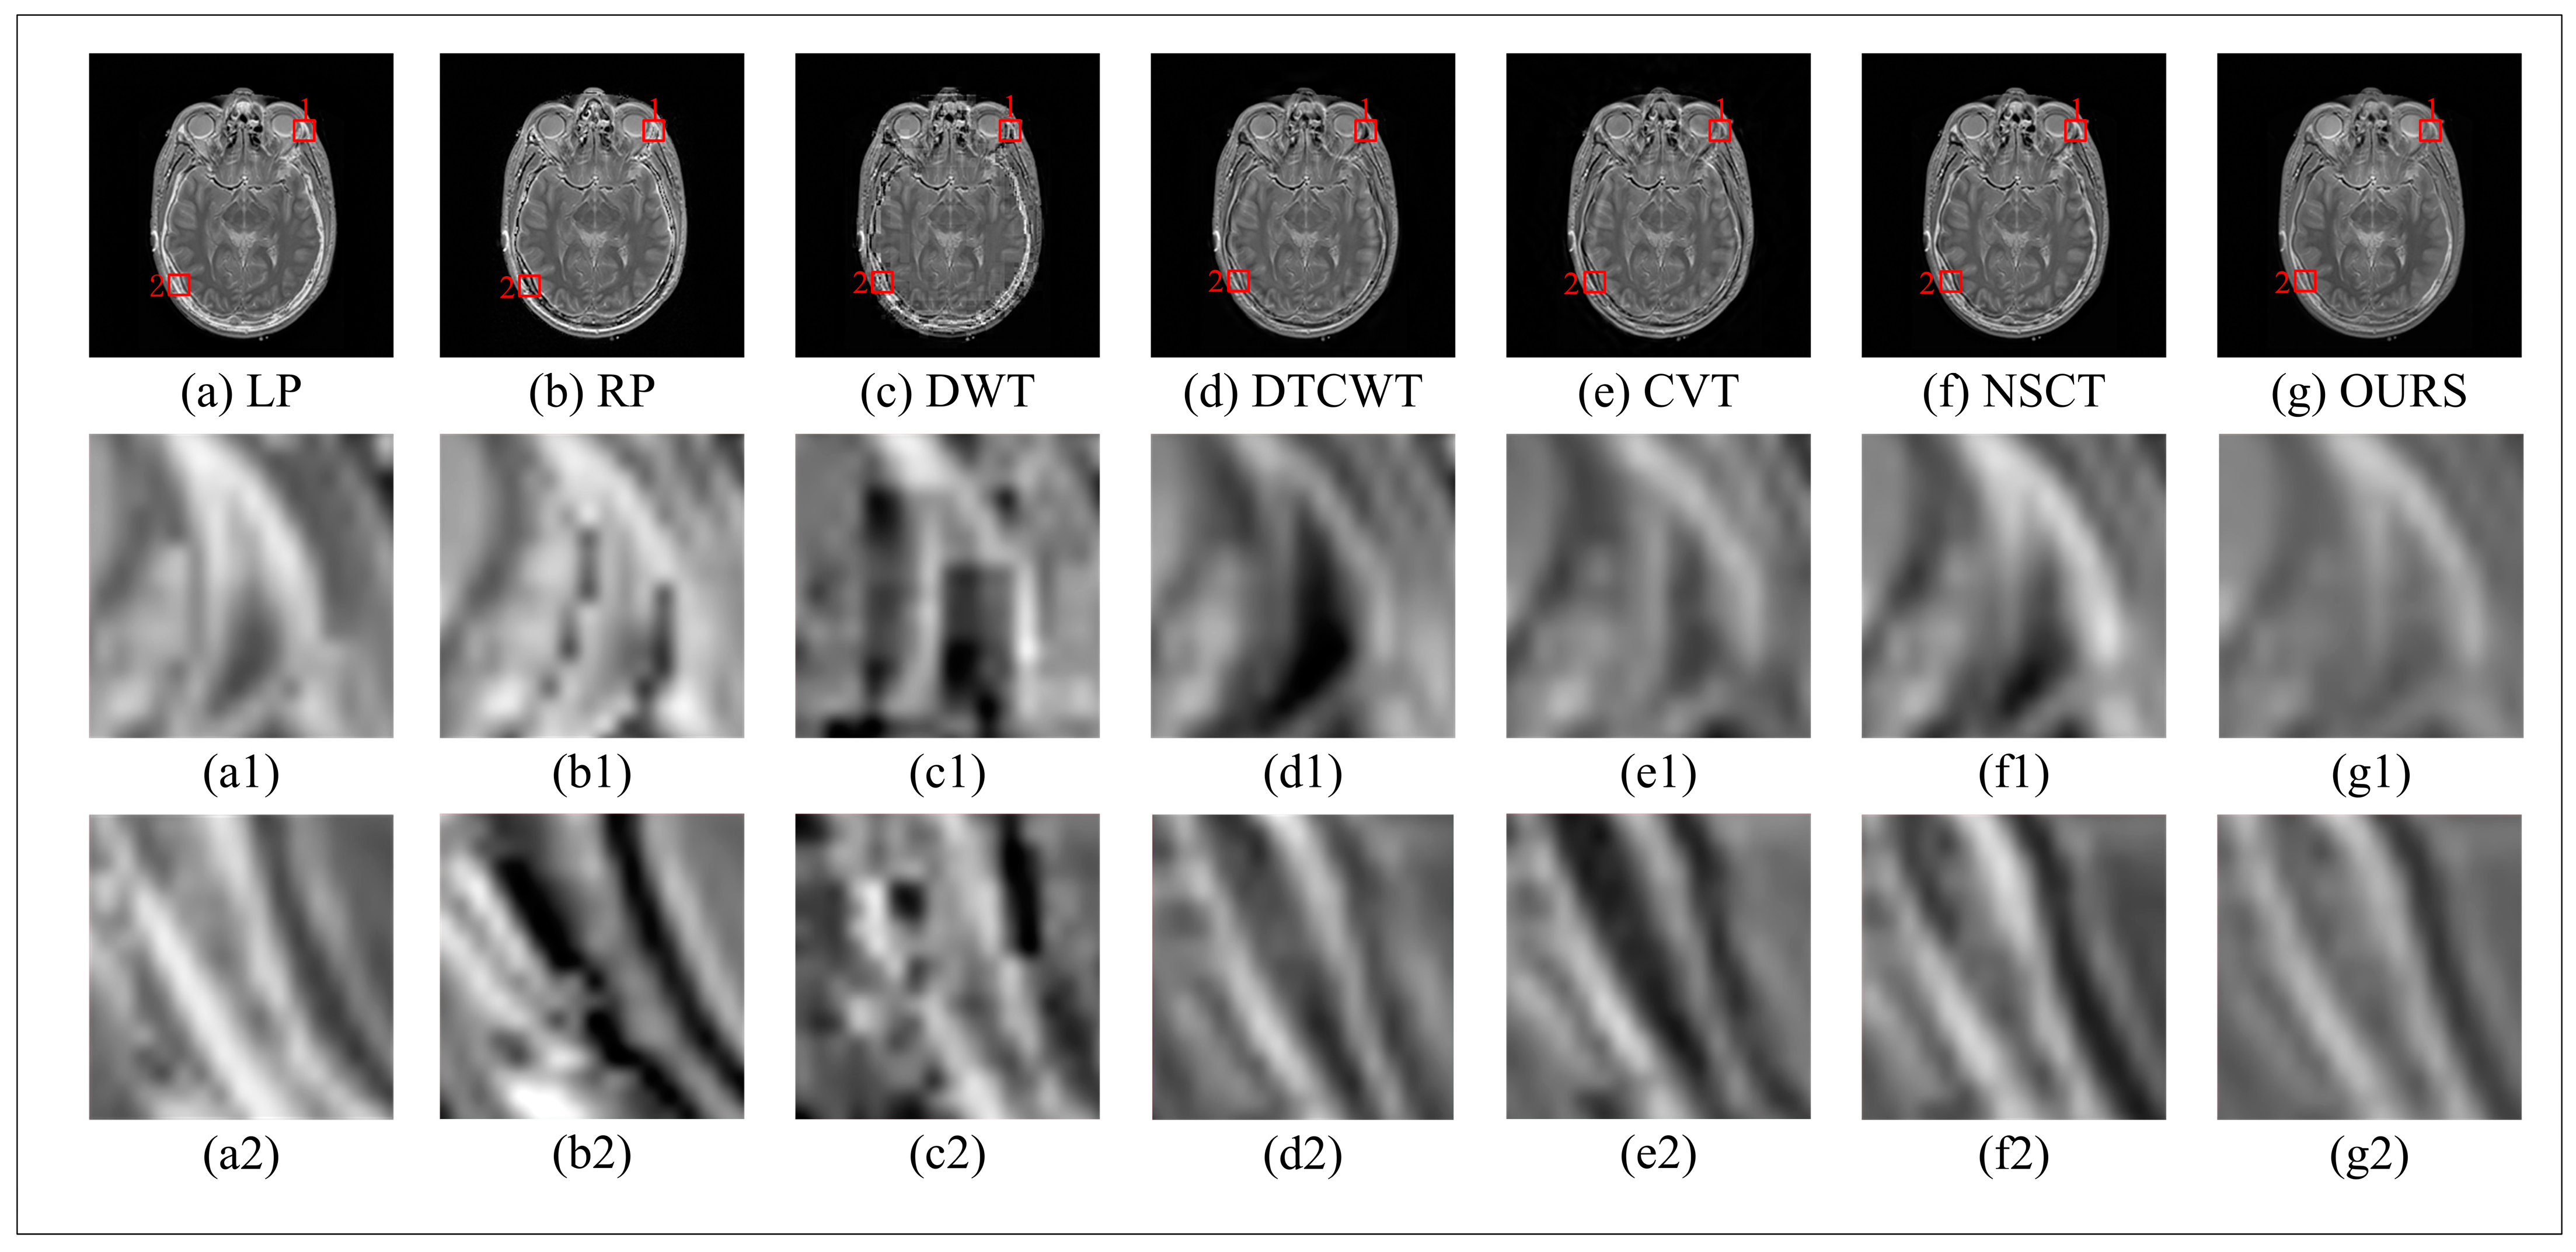

Figure 11 is the detail diagram of multi-modal medical image fusion. The algorithms RP, LP, DTCWT CVT, and NSCT show blocky segmentation and unsmooth edges in detail 1 and 2. We use Gaussian filtering to reduce noise and unsmooth problems caused by interpolation. In image fusion, the method of overlapping segmentation is used to make the edge of the image smoother.

Figure 11.

Comparison of different algorithms for medical multi-model image fusion. (a) LP algorithm, (b) RP algorithm, (c) DWT algorithm, (d) DTCWT algorithm, (e) CVT algorithm, (f) NSCT algorithm, (g) our algorithm.